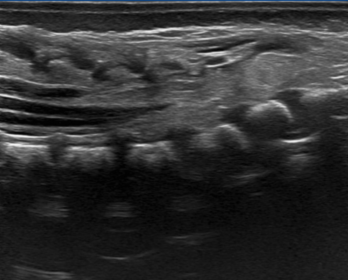

Durante su ingreso se realiza estudio ecográfico en el que se objetiva una masa grasa subcutánea en región glútea izquierda adyacente al pliegue interglúteo, que se continúa a través de un defecto de fusión de los elementos posteriores espinales con el saco tecal y el cono medular, que se muestra descendido (Figura 2). Estos hallazgos son compatibles con la presencia de un lipomielomeningocele y una médula anclada a la altura de L5, por lo que ampliamos el estudio con resonancia magnética (RM) (Figura 3) confirmando la presencia de un disrafismo espinal cerrado.

Una vez que se han detectado los marcadores cutáneos sospechosos, es necesario descartar el diagnóstico de DEO, para lo que se han utilizado distintas técnicas, siendo la RM del canal medular en toda su extensión el examen de primera elección para la detección, determinar la extensión intraespinal y la localización exacta del cono medular. Así pues, la ecografía lumbosacra se muestra útil para el screening en niños menores de 4-6 meses gracias a la ausencia de osificación completa de la columna, lo que posibilita una buena ventana acústica, como se realizó en el caso que presentamos como primera prueba diagnóstica por su accesibilidad, optando por la RM como prueba confirmatoria.